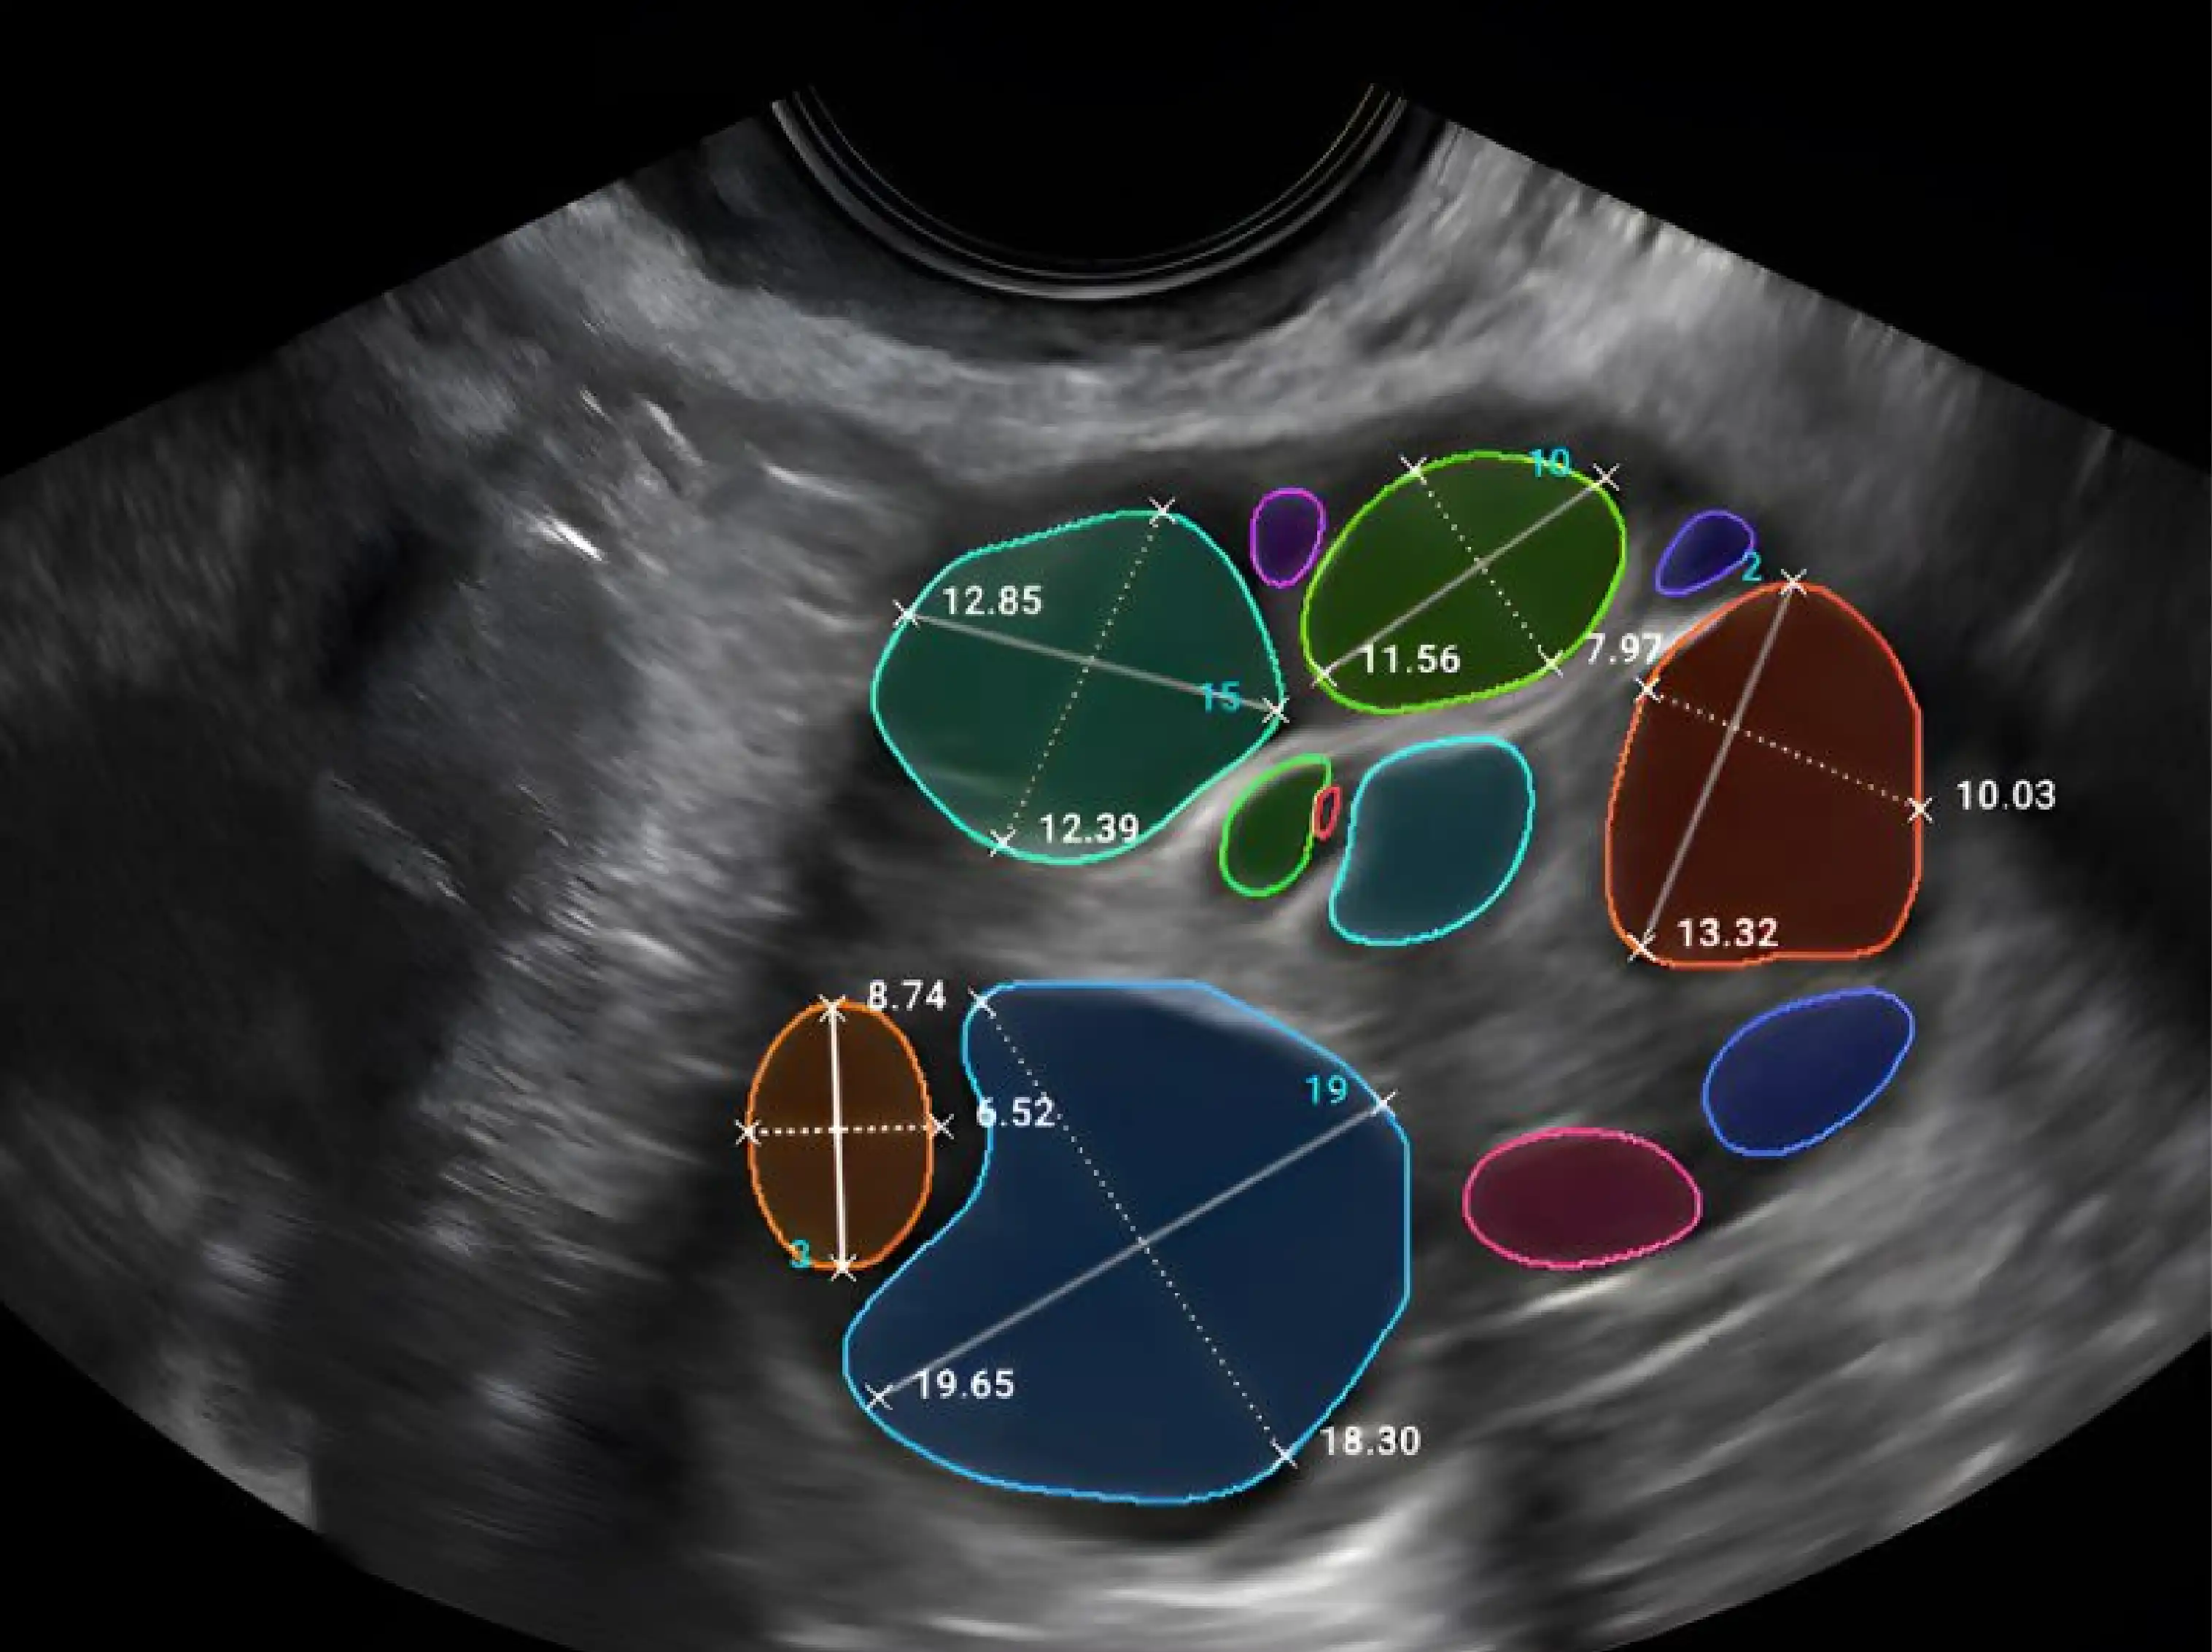

نسعى لتزويد مراكز وأبحاث التلقيح الصناعي بأجهزة مختبرية عالية الجودة، مثل حاضنات الأجنة طويلة الأمد، محطات تقنيات الإنجاب المساعدة (ART)، طاولات مضادة للاهتزاز، حاضنات بتقنية التوقيت الزمني، ليزر طبي، محطات ICSI وIMSI، بالإضافة إلى المستلزمات والأجهزة المحمولة.

• صور دقيقة للأجنة بتقنية التوقيت الزمني.